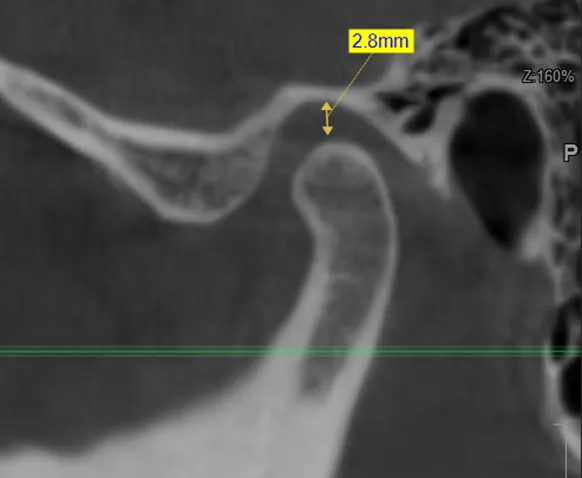

• компьютерная томография (КТ),